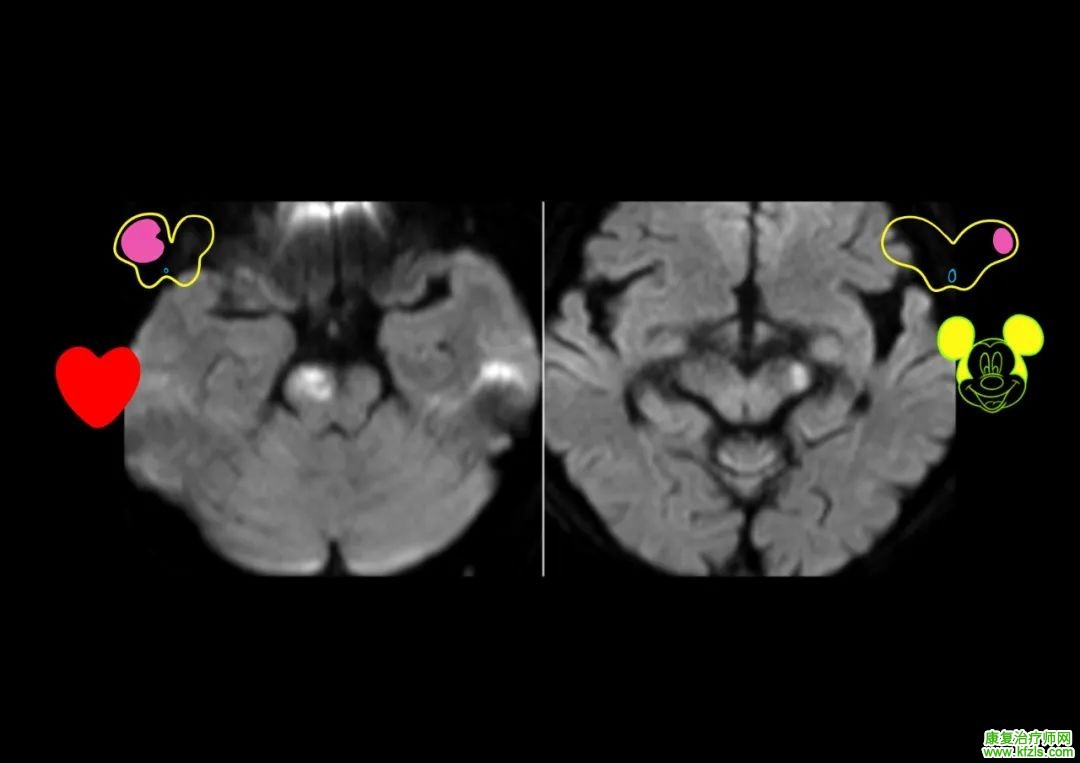

55 岁女性,主因「视物重影、行走不稳 6 天,左眼睑下垂 5 天」入院。查体:左眼睑下垂,左瞳孔 4 mm,光反射迟钝,右瞳孔 3 mm,光反射灵敏,左眼内收、上下运动受限,左眼各方向活动可,右侧指鼻试验及跟膝胫试验不稳,Romberg 征阳性。头颅核磁如下:

脑干梗死

病例来源:参考文献